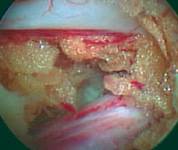

Эндоскопическое изображение операционного поля |